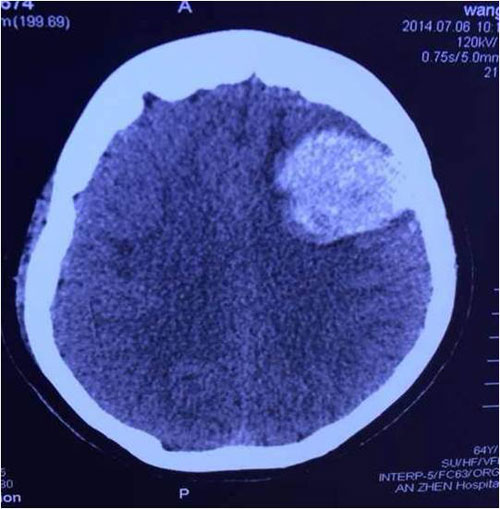

- 术后第2天患者出现呕吐、失语等症状,行急诊CT示:左侧额叶区见类圆形高密度灶,病灶大小为43.9×33.2 mm,左脑室轻度轻度受压,移位变形,出血量约30 ml(图2)。

图2.头颅 CT提示脑出血